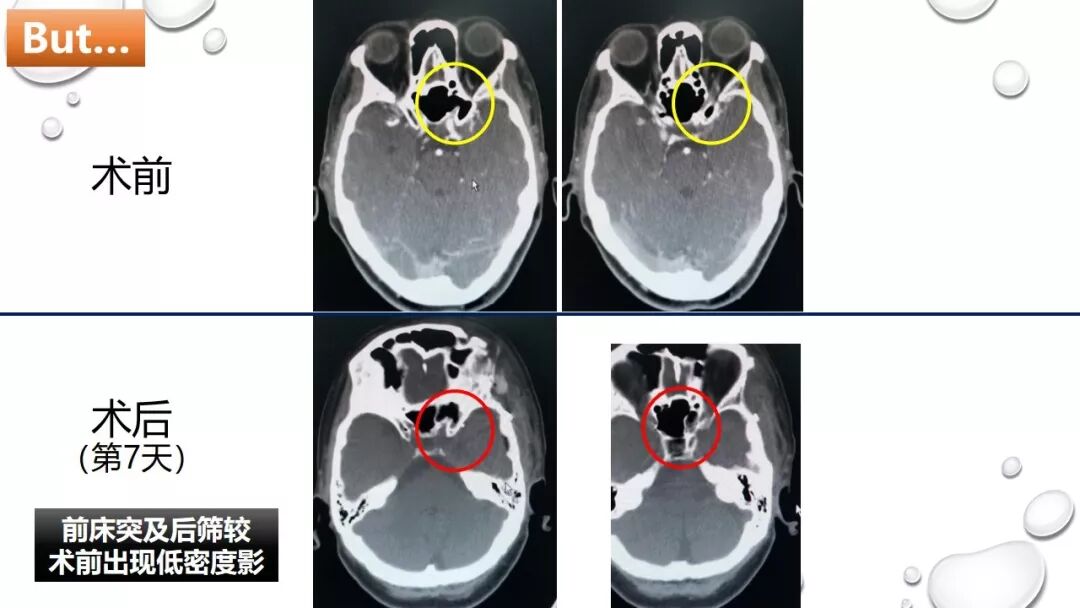

前床突磨除